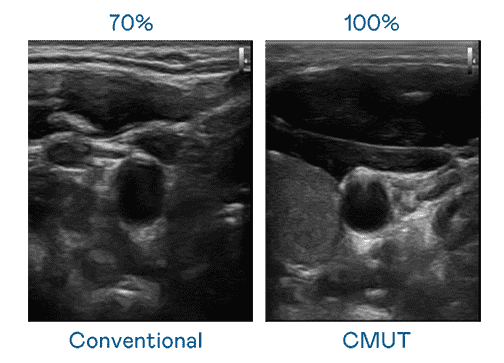

CMUT 技术是一种用电容式微机电元件来产生超音波讯号的技术。。。与传统 PZT 压电式技术相比,,,,CMUT 频宽增加 30%,,,更宽频的超音波讯号让影像解析度大幅提升,,,是实现高影像品质医疗超音波扫描、、、、促进精准医疗发展的关键技术。。。

大频宽带来超清晰影像

超音波影像的解析度高低,,,,首先取决于探头能发出的讯号频宽。。。传奇国际 CMUT 可提供高清晰的超音波讯号,,提供高频宽、、、、高灵敏度、、、影像纹理细节更高的超音波影像,,,,协助医护人员缩短影像判读时间及利用精准的医疗影像进行诊断。。。。